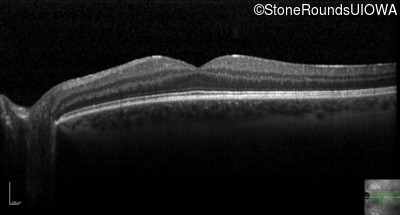

Optical Coherence Tomography - Right - 20/15 -1 sc

Exemplar / OCT Stack

OCT Stack